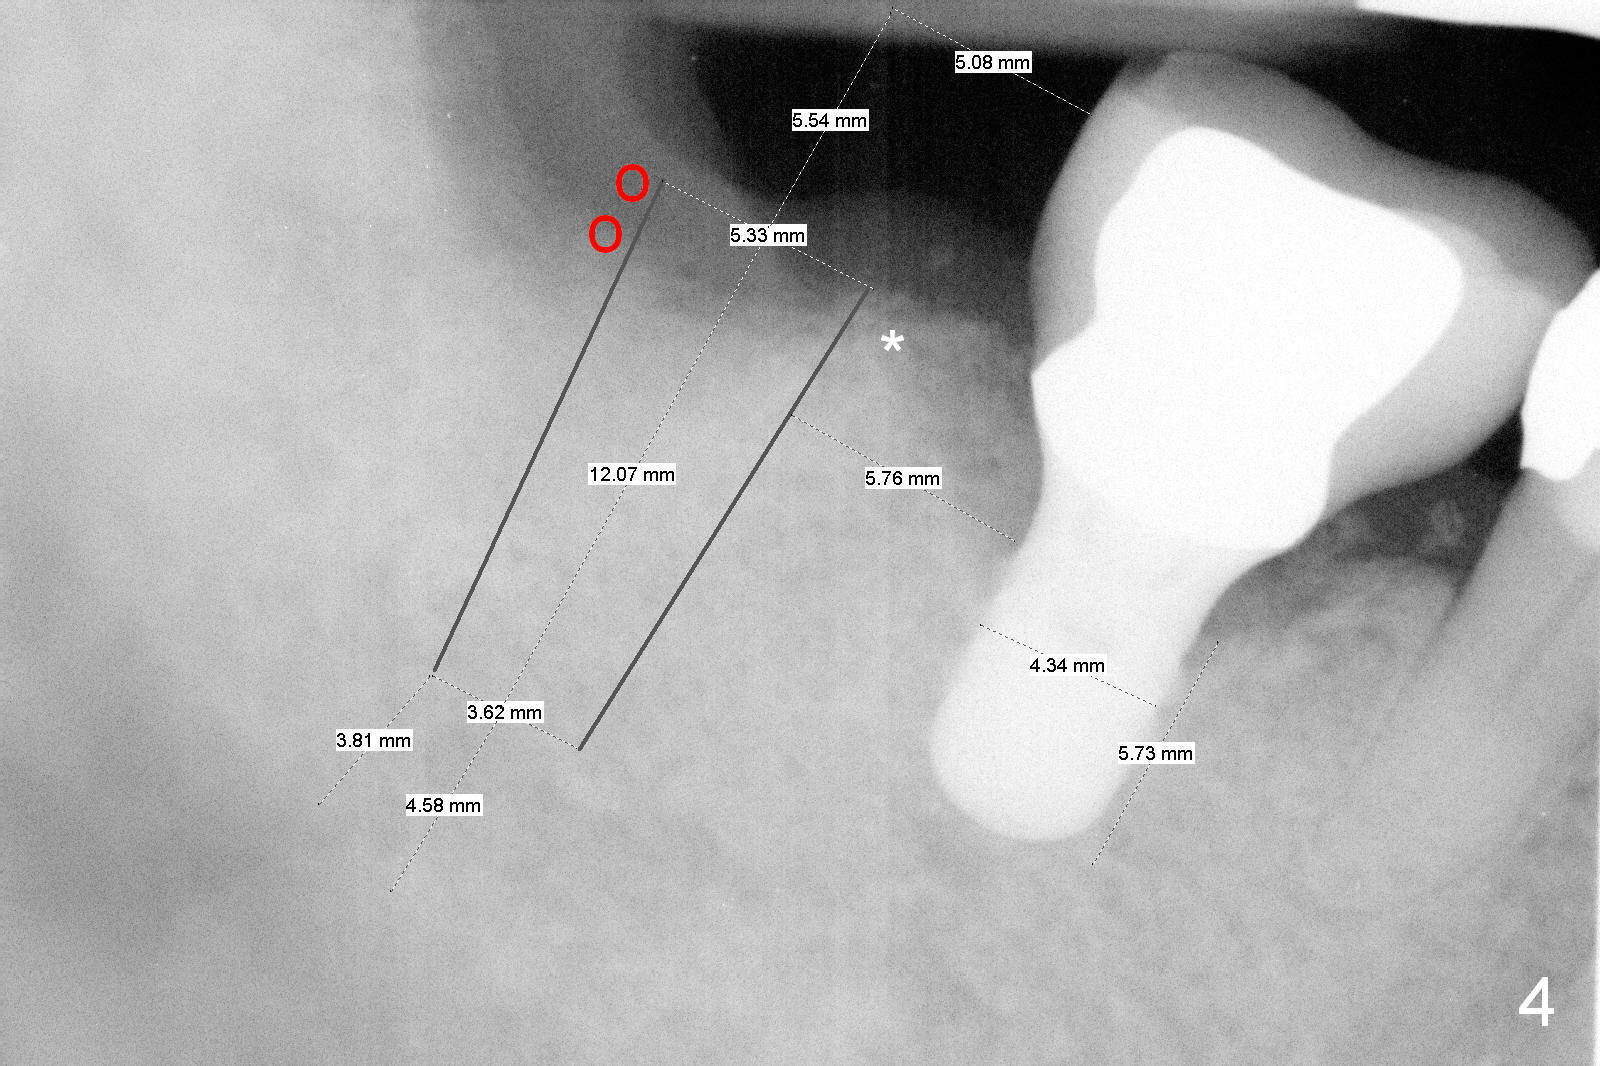

The design in Fig.4 overcomes these 2 shortcomings. The center of the implant is 5 mm from the neighboring tooth. Mesially there is more bone support (*), whereas distally bone graft is necessary (red circles). There is still enough space between the two implants; the minimum is 3 mm.

No matter which design, there is possibility of the buccal threads of the implant. Bone graft is expected. Collagen dressing should be cut in a ring shape, fixed by an abutment.